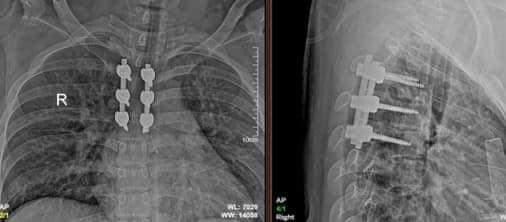

Kết quả chụp cộng hưởng từ (MRI) cột sống ngực có khối máu tụ chèn ép tủy ngang mức D3D4. Bệnh nhân đã được hội chẩn và phẫu thuật mở cung sau đốt sống D3D4 giải ép, cố định cột sống.

Bác sĩ Lã Quang Thịnh - Phó Trưởng khoa Chấn thương chỉnh hình - Bệnh viện đa khoa Hùng Vương thông tin, đây là một trường hợp hiếm gặp, bệnh nhân có thể gặp chấn thương do tập gym quá sức, sai tư thế, rất may bệnh nhân đã đến viện sớm và được phẫu thuật kịp thời. Khi tủy sống bị chèn ép, bệnh nhân có nguy cơ bị liệt hai chi dưới phải ngồi xe lăn suốt đời.

Theo bác sĩ Thịnh, sau mổ bệnh nhân diễn biến ổn định, phục hồi tốt và đang được các bác sĩ theo dõi - (ảnh BVCC).

Theo bác sĩ Thịnh, sau mổ bệnh nhân diễn biến ổn định, phục hồi tốt và đang được các bác sĩ theo dõi.